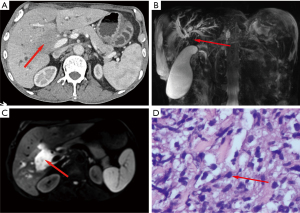

The contrast-enhanced upper abdominal CT demonstrated the following: (I) intrahepatic biliary duct dilatation; (II) biliary stricture at the hepatic hilum; and (III) suspicious enhancing lesions exhibiting delayed-phase enhancement with encasement of the portal vein (Figure 2A). Complementary magnetic resonance cholangiopancreatography (MRCP) demonstrated clustered soft tissue abnormalities at the same site, displaying characteristic signal patterns: T1 hypointensity, T2 hyperintensity, and diffusion-weighted imaging (DWI) hyperintensity (Figure 2B,2C)—imaging features supporting a cholangiocarcinoma diagnosis.

Multidisciplinary team (MDT) discussions and literature review yielded no reported cases of myeloma with hilar bile duct metastasis. Elevated CA199 levels and imaging findings (CT and MRCP) supported a diagnosis of hilar cholangiocarcinoma. Given the patient’s myeloma history, a porta hepatis biopsy was performed to confirm the diagnosis and rule out metastasis.

Following family consent, CT-guided biopsy of the hilar bile duct mass was performed on 5 September 2023. Histopathological analysis integrating morphology, immunohistochemistry [syndecan-1 (CD138)(3+), cluster of differentiation 38 (CD38)(1+), multiple myeloma oncogene 1 (MUM1; 2+), antigen identified by monoclonal antibody Ki-67 (Ki-67; 40%+), with negative cluster of differentiation 56 (CD56)/cytokeratin 7 (CK7)/cytokeratin 19 (CK19)/cluster of differentiation 20 (CD20)], and clinical jaundice history confirmed a plasma cell neoplasm, indicating metastatic bone marrow tumor to the biliary system (Figure 2D). These findings established a final diagnosis of MM with hilar bile duct involvement, ruling out primary cholangiocarcinoma. The patient was subsequently transferred to the hematology department for specialized care on 13 September 2023.